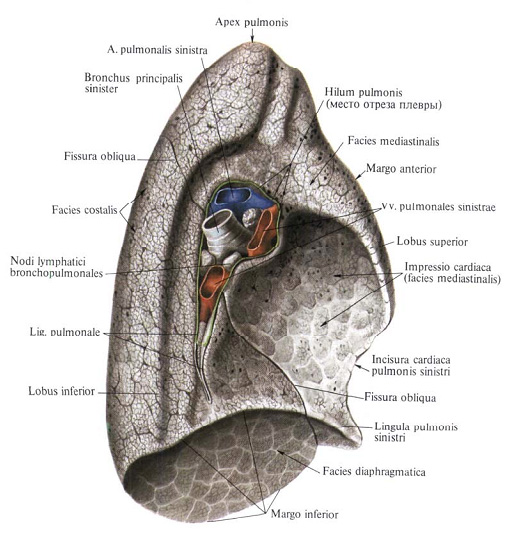

Анатомические изображения сегментов легких различных животных

Раздел: Другие животные